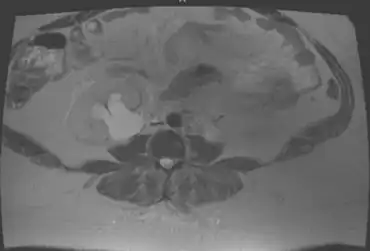

Individual with pelvic malakoplakia showing hydronephrosis